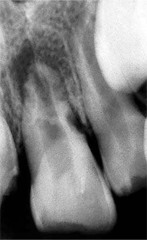

periapical granuloma

-asymptomatic, tooth sensitive to percussion, slight extrusion of tooth -radiographically: slight thickening PDL and periodontal radiolucency CHRONIC